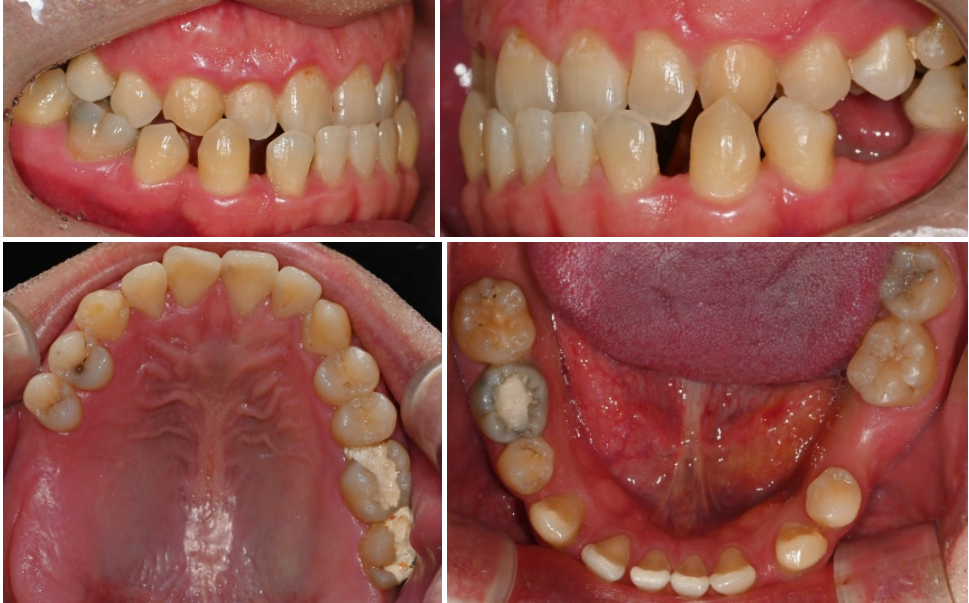

| 주걱턱과 치아 결손, 반대교합의

| 복합적 문제

주걱턱은 아래턱이 위턱보다

과도하게 앞으로 나온 상태로,

골격적 문제와 치아 배열 문제가

복합적으로 나타나는 경우가 많아요.

이런 상황에서 치아 결손까지

같이 있으면 문제가 더욱 복잡해집니다.

특히 주걱턱과 함께 나타나면

아래턱의 돌출이 더욱 심해 보이고,

얼굴 전체의 균형이 더욱

불안정해질 수 있어요.

결손된 치아 부위에서는

음식물을 제대로 씹을 수 없어

한쪽으로만 씹는 습관이 생기고,

이는 턱관절에 불균형을 일으킵니다.

또한 치아 결손으로 인한

공간 때문에 개방교합이 더욱 심해질 수 있고,

반대교합도 악화될 위험이 높아요.